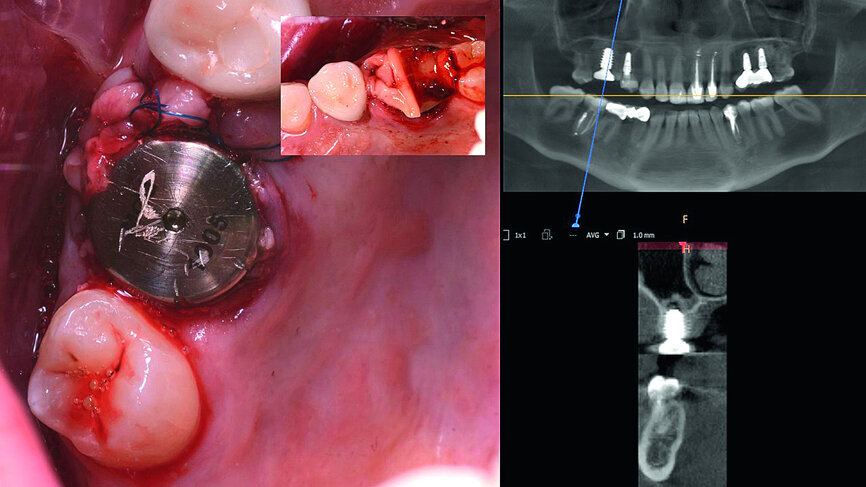

In November 2017, a 39-year-old female patient came to an initial appointment at White Clinic owing to tooth pain (tooth #16). A clinical and radiographic examination were performed, including a periapical radiograph, CBCT scan (Carestream 9500, Carestream Dental), and intra- and extraoral photographs (Figs. 1–3).

In the clinical and radiographic evaluation, it was observed that tooth #16 presented an invasive cervical resorption at the mesiobuccal root. The treatment plan established was dental extraction with immediate implant placement. The tooth had been previously re-treated endodontically and restored with a definitive ceramic crown. Due to the current situation of the tooth, although the protocol in White Clinic is to preserve teeth, it had indication for immediate extraction. Also due to the lack of time, our digital team was not able to produce a surgical guide for the implant placement. Therefore, the treatment plan included a surgical phase and a digital prosthetic phase.

The surgical treatment phase started with extraction of tooth #16, followed by excision of the root cyst and alveolar curettage (Figs. 4a & b). For good disinfection of the alveolus, ozone therapy (Ozone DTA, Apoza) was applied (Fig. 4c), taking into account the antimicrobial action of ozone, which prevents the development of the inflammatory process, favouring cellular recovery and consequently improving the postoperative healing. Once the alveolus had been disinfected, the implant bed was prepared with a sequence of implant drills from the AnyRidge surgical system (AnyRidge Surgical Kit, MegaGen; Fig. 4d). The bone defects were filled with a bone xenograft of porcine origin (Gen-Os, OsteoBiol), mixed with i-PRF (injectable platelet-rich fibrin; PRF process by Choukroun; Figs. 5a & b). Afterwards, bone densification was performed through a sequence of Densah drills (Densah Burs, Versah; Fig. 6a). This type of drill allows the clinician to perform a bone densification process.

Once the implant bed had been prepared, a 7 × 10 mm implant (AnyRidge) was placed. After placement, the ISQ (Implant Stability Quotient) was measured with a stability meter (Mega ISQ, MegaGen), and the value was 72. According to the ISQ scale, this represents high stability (Fig. 6b). A 10 × 7 mm healing screw (AnyRidge) was placed, along with a plug of A-PRF (advanced platelet-rich fibrin; PRF process by Choukroun) in order to accelerate the healing process, and sutured with 4/0 polypropylene (Hu-Friedy; Figs. 7–10). After the surgical procedure, the White Clinic postoperative protocol was applied: application for eight minutes of the ATP38 laser (Swiss Bio Inov), based on the principle of Low Level Laser Therapy that acts on the cellular metabolism and provides a better and faster postoperative healing. The patient was instructed to use a 0.2% hyaluronic acid gel (Gengigel, Ricerfarma) and 0.1% hyaluronic acid mouthwash (Gengigel First-aid, Ricerfarma) for one week after surgery, with the goal of accelerating the healing process. One week after surgery, the sutures were removed, ozone was used to disinfect the area around the implant, and the ATP38 was applied for eight minutes to promote healing.